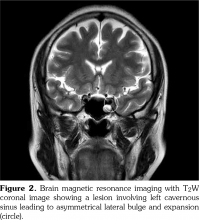

A 53-year-old female patient visited our clinic with complaints of sudden onset of orbital pain, ipsilateral headache and intermittent diplopia. The severe, lancinating pain was aggravated with eyeball movements. Previously, she had been diagnosed with BD based on recurrent oral and genital ulcers and a positive pathergy test. She tested positive for human leucocyte antigen B51. She remained on colchicine 1.2 mg/day and had been asymptomatic for 12 years. She denied a history of hypertension, diabetes, malignancy, asthma or hyperthyroidism. The pupils reacted normally to light and were of equal size. Visual acuity was 20/20 in each eye. Mild hypertropia was observed on the left. Limited inferior rectus movement was found among the nine cardinal extraocular movements associated with diplopia (Figure 1). Neither papilledema nor raised intraocular pressure was found. The remaining neurological examination was normal. Laboratory parameters including complete blood count, muscle enzymes, sedimentation rate, C-reactive protein, antinuclear antibodies, double-stranded deoxyribonucleic acid antibodies, anti-neutrophil cytoplasmic antibodies, C3, C4 antiphospholipid, anticardiolipin, and β2 glycoprotein antibodies, proteins C and S, and thyroid function were all within normal range. Magnetic resonance imaging (MRI) of the brain demonstrated bulging and expansion of the left cavernous sinus (Figure 2) due to thrombosis. Cerebrospinal fluid examination was unrevealing. Finally, she was diagnosed with Tolosa-Hunt-like syndrome associated with BD. The patient was started on a course of intravenous methylprednisolone (1 g/day for five days). On day three of the treatment, she had a considerable relief of retro-orbital pain and headache. Two weeks later, noticeable improvement in ophthalmoplegia was observed following treatment with oral prednisolone 50 mg/day. After eight weeks, she showed complete resolution of diplopia. Six months later, the patient remained on oral prednisolone 7.5 mg/day without recurrence.